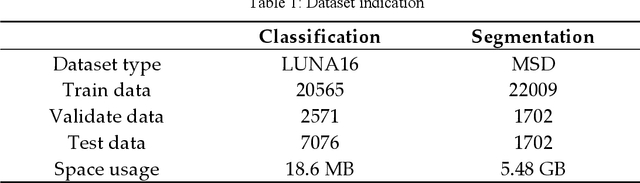

With the development of computer technology, various models have emerged in artificial intelligence. The transformer model has been applied to the field of computer vision (CV) after its success in natural language processing (NLP). Radiologists continue to face multiple challenges in today's rapidly evolving medical field, such as increased workload and increased diagnostic demands. Although there are some conventional methods for lung cancer detection before, their accuracy still needs to be improved, especially in realistic diagnostic scenarios. This paper creatively proposes a segmentation method based on efficient transformer and applies it to medical image analysis. The algorithm completes the task of lung cancer classification and segmentation by analyzing lung cancer data, and aims to provide efficient technical support for medical staff. In addition, we evaluated and compared the results in various aspects. For the classification mission, the max accuracy of Swin-T by regular training and Swin-B in two resolutions by pre-training can be up to 82.3%. For the segmentation mission, we use pre-training to help the model improve the accuracy of our experiments. The accuracy of the three models reaches over 95%. The experiments demonstrate that the algorithm can be well applied to lung cancer classification and segmentation missions.